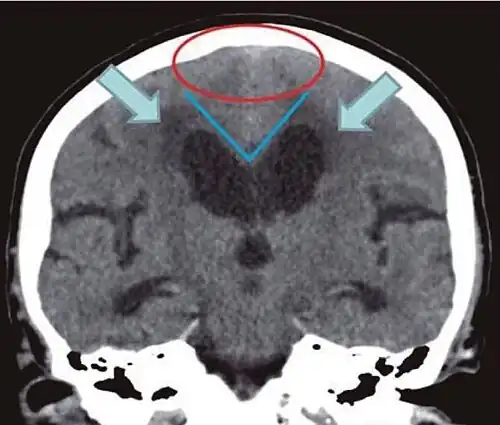

- Imaging from magnetic resonance imaging (MRI) or computed tomography (CT) is needed to demonstrate enlarged ventricles and no macroscopic obstruction to cerebrospinal fluid flow. Imaging should show an enlargement to at least one of the temporal horns of lateral ventricles, and impingement against the falx cerebri resulting in a callosal angle ≤ 90° on the coronal view, showing evidence of altered brain water content, or normal active flow (which is referred to as "flow void") at the cerebral aqueduct and fourth ventricle.

| Normal pressure hydrocephalus | Brain atrophy | |

| Preferable projection | Coronal plane at the level of the posterior commissure of the brain. | |

| Modality in this example | CT | MRI |

| CSF spaces over the convexity near the vertex (red ellipse |

Narrowed convexity ("tight convexity") as well as medial cisterns | Widened vertex (red arrow) and medial cisterns (green arrow) |

| Callosal angle (blue V) | Acute angle | Obtuse angle |

| Most likely cause of leucoaraiosis (periventricular signal alterations, blue arrows |

Transependymal cerebrospinal fluid diapedesis | Vascular encephalopathy, in this case suggested by unilateral occurrence |

MRI scans are the preferred imaging. The distinction between normal and enlarged ventricular size by cerebral atrophy is difficult to ascertain. Up to 80% of cases are unrecognized and untreated due to difficulty of diagnosis.[22] Imaging should also reveal the absence of any cerebral mass lesions or any signs of obstructions. Although all patients with NPH have enlarged ventricles, not all elderly patients with enlarged ventricles have primary NPH. Cerebral atrophy can cause enlarged ventricles, as well, and is referred to as hydrocephalus ex vacuo. For these reasons it's utmost important to note that Evan's index although commonly used in imaging is not very specific for NPH. One recent systematic review and meta-analysis suggests that callosal angle has high diagnostic performance and is commonly used together with Evan's index.[23]